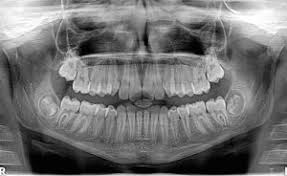

(the atmosphere acts to absorb or deflect some of the cosmic radiation. The lowest radiation exposure to cause radiation sickness is about 100 rem (1 sv). More images for how many x rays are safe in a year » This level of exposure will also increase your risk of a fatal cancer over the next few to several decades by about 5%. What matters is the intensity of the radiation. How are x rays harmful to the earth? What are the hazards of x rays? You have to understand that the frequency of the radiation doesn't matter. How many x rays are dangerous? The dosage is less and the image quality has improved. The exposure we are concerned about is lifetime exposure, not annual exposure. Those who don't have cavities can go a year or two between. Why are x rays dangerous?

What are the hazards of x rays? In the case of standard procedures, there is no or negligible chance of risk. They are advised only at certain ages. This level of exposure will also increase your risk of a fatal cancer over the next few to several decades by about 5%. (the atmosphere acts to absorb or deflect some of the cosmic radiation. How many x rays are dangerous? The lowest radiation exposure to cause radiation sickness is about 100 rem (1 sv). The exposure we are concerned about is lifetime exposure, not annual exposure. The dosage is less and the image quality has improved. More images for how many x rays are safe in a year » Why are x rays dangerous? Those who don't have cavities can go a year or two between. What matters is the intensity of the radiation.

(the atmosphere acts to absorb or deflect some of the cosmic radiation. What are the hazards of x rays? More images for how many x rays are safe in a year » The dosage is less and the image quality has improved. How are x rays harmful to the earth? They are advised only at certain ages. Those who don't have cavities can go a year or two between. This level of exposure will also increase your risk of a fatal cancer over the next few to several decades by about 5%. Why are x rays dangerous? How many x rays are dangerous? The exposure we are concerned about is lifetime exposure, not annual exposure. The lowest radiation exposure to cause radiation sickness is about 100 rem (1 sv). You have to understand that the frequency of the radiation doesn't matter.